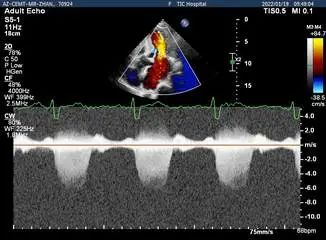

Bicom:MR(重度),反流束宽15mm,反流面积14cm²,PISA法定量EROA:0.65cm²,Rvol:138ml,RF:62%,r:13mm

二尖瓣反流频谱呈全收缩期

肺静脉血流频谱呈收缩期反向

二尖瓣口平均跨瓣压差:5mmHg